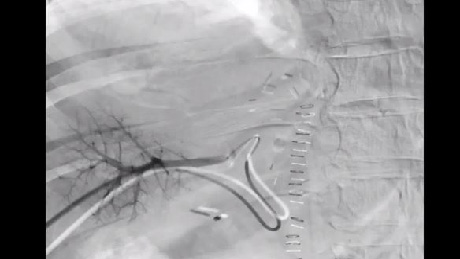

This image shows how the Direxion Microcatheter tracked through a severe, near 180-degree angulation of the right hepatic artery in order to complete the embolization.